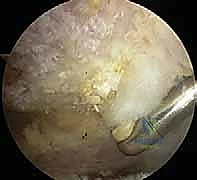

الخطوة الثانية: إزالة الكيس الزلالي الملتهب (Bursectomy)

يتم توجيه المنظار إلى الحيز تحت الأخرم (Subacromial space). غالباً ما يكون هذا الحيز مليئاً بالأنسجة الالتهابية والكيس الزلالي المتضخم الذي يعيق الرؤية ويسبب الألم. باستخدام أداة دقيقة تسمى "الشاڤر" (Shaver) وجهاز التردد الحراري (Radiofrequency wand)، يتم تنظيف وإزالة هذا النسيج الملتهب بالكامل لكشف السطح السفلي لعظم الأخرم وأوتار الكفة المدورة.